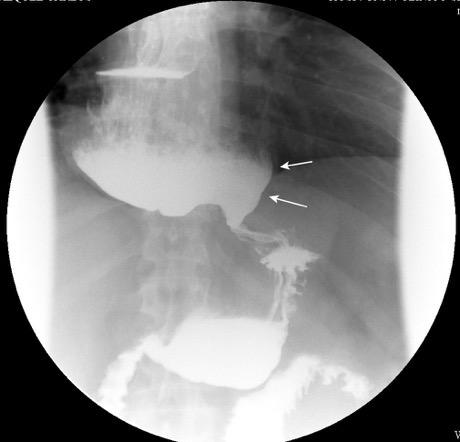

“Seudoquiste pancreático”

Seudoquiste pancreático

3 rasgos:

1. Conexión entre mediastino y lesión pancreática.

2. Derrame pleural

Matsusue E et al.Three cases of mediastinal pancreatic pseudocysts. Acta Radiol Open. 2016 .

3. Hallazgos de pancreatitis. Panda A et al. “Straddling Across Boundaries”. Thoracoabdominal Lesions: Spectrum and Pattern Approach.Curr Probl Diagn Radiol, 2015